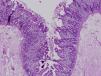

La diarrea secretora comenzó en el primer mes de vida en los 3 pacientes. Una era mujer y 2, varones. La primera paciente era de nacionalidad ecuatoriana y los 2 últimos eran hermanos, de origen marroquí y nacidos de padres consanguíneos. Todos fueron recién nacidos a término y presentaron un peso adecuado al nacimiento. Las ecografías prenatales fueron normales. Ninguno de los pacientes presentó atresia ni queratitis puntiforme. El estudio inmunológico fue normal. El estudio histológico de la mucosa intestinal demostró acortamiento de las vellosidades y agrupaciones de enterocitos de que formaban penachos (figs. 1 y 2). En el segundo y tercer paciente se confirmó la existencia de mutación en el gen EpCAM en homocigosis. Se detectó una deleción intragénica de 17 bases (c.352_368del, NM_002354,2). No se realizó estudio genético en la primera paciente.

El diagnóstico se basa en la demostración de los hallazgos histológicos típicos de esta enfermedad. Al microscopio óptico se objetiva una atrofia vellositaria intensa, con hiperplasia críptica y ausencia de infiltrado inflamatorio en la lámina propia. El hallazgo característico son los acúmulos de enterocitos empaquetados, que confieren un borde romo a la vellosidad y constituyen los penachos a que alude el nombre de esta entidad1. En la microscopia electrónica los hallazgos ultraestructurales que acompañan a los penachos de enterocitos son un discreto acortamiento del borde en cepillo y un aumento en el número y la longitud de los desmosomas entre enterocitos. Mediante la inmunohistoquímica MOC31 se tiñe, en condiciones normales, el epitelio de la mucosa, sin observarse tinción de la lámina propia ni de los vasos. En los casos de DEI existe una ausencia completa de tinción de la superficie epitelial, criptas y penachos. Algunos pacientes asocian rasgos dismórficos, atresia esofágica, atresia de coanas y anorrectal4. Y hasta el 60% de los pacientes presenta queratitis puntiforme4.